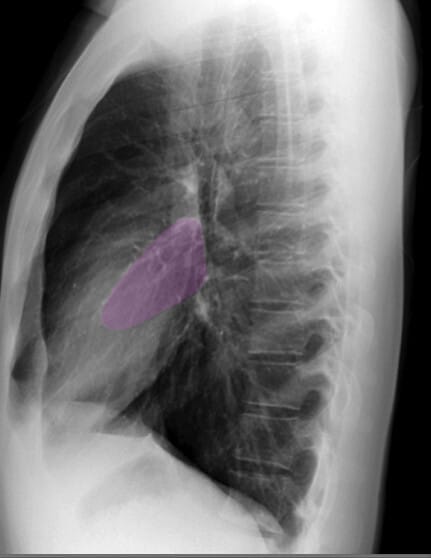

Lateral View of Chest X-ray

측면 영상은 폐, 심장 및 척추의 깊이를 평가하는 데 유용합니다.

| 좌심방 (Left Atrium) |

| ✅ 좌심방은 측면 영상에서 심장 후방에 위치하며, 기관(trachea) 바로 앞쪽에 위치합니다. 좌심방이 확장되면 기관이 뒤로 밀리는 소견이 나타날 수 있습니다. |

| 좌심실 (Left Ventricle) |

| ✅ 좌심실은 심장의 가장 하부와 후방을 차지하며, 비대해지면 좌측 횡격막과의 경계가 불명확해질 수 있습니다. |